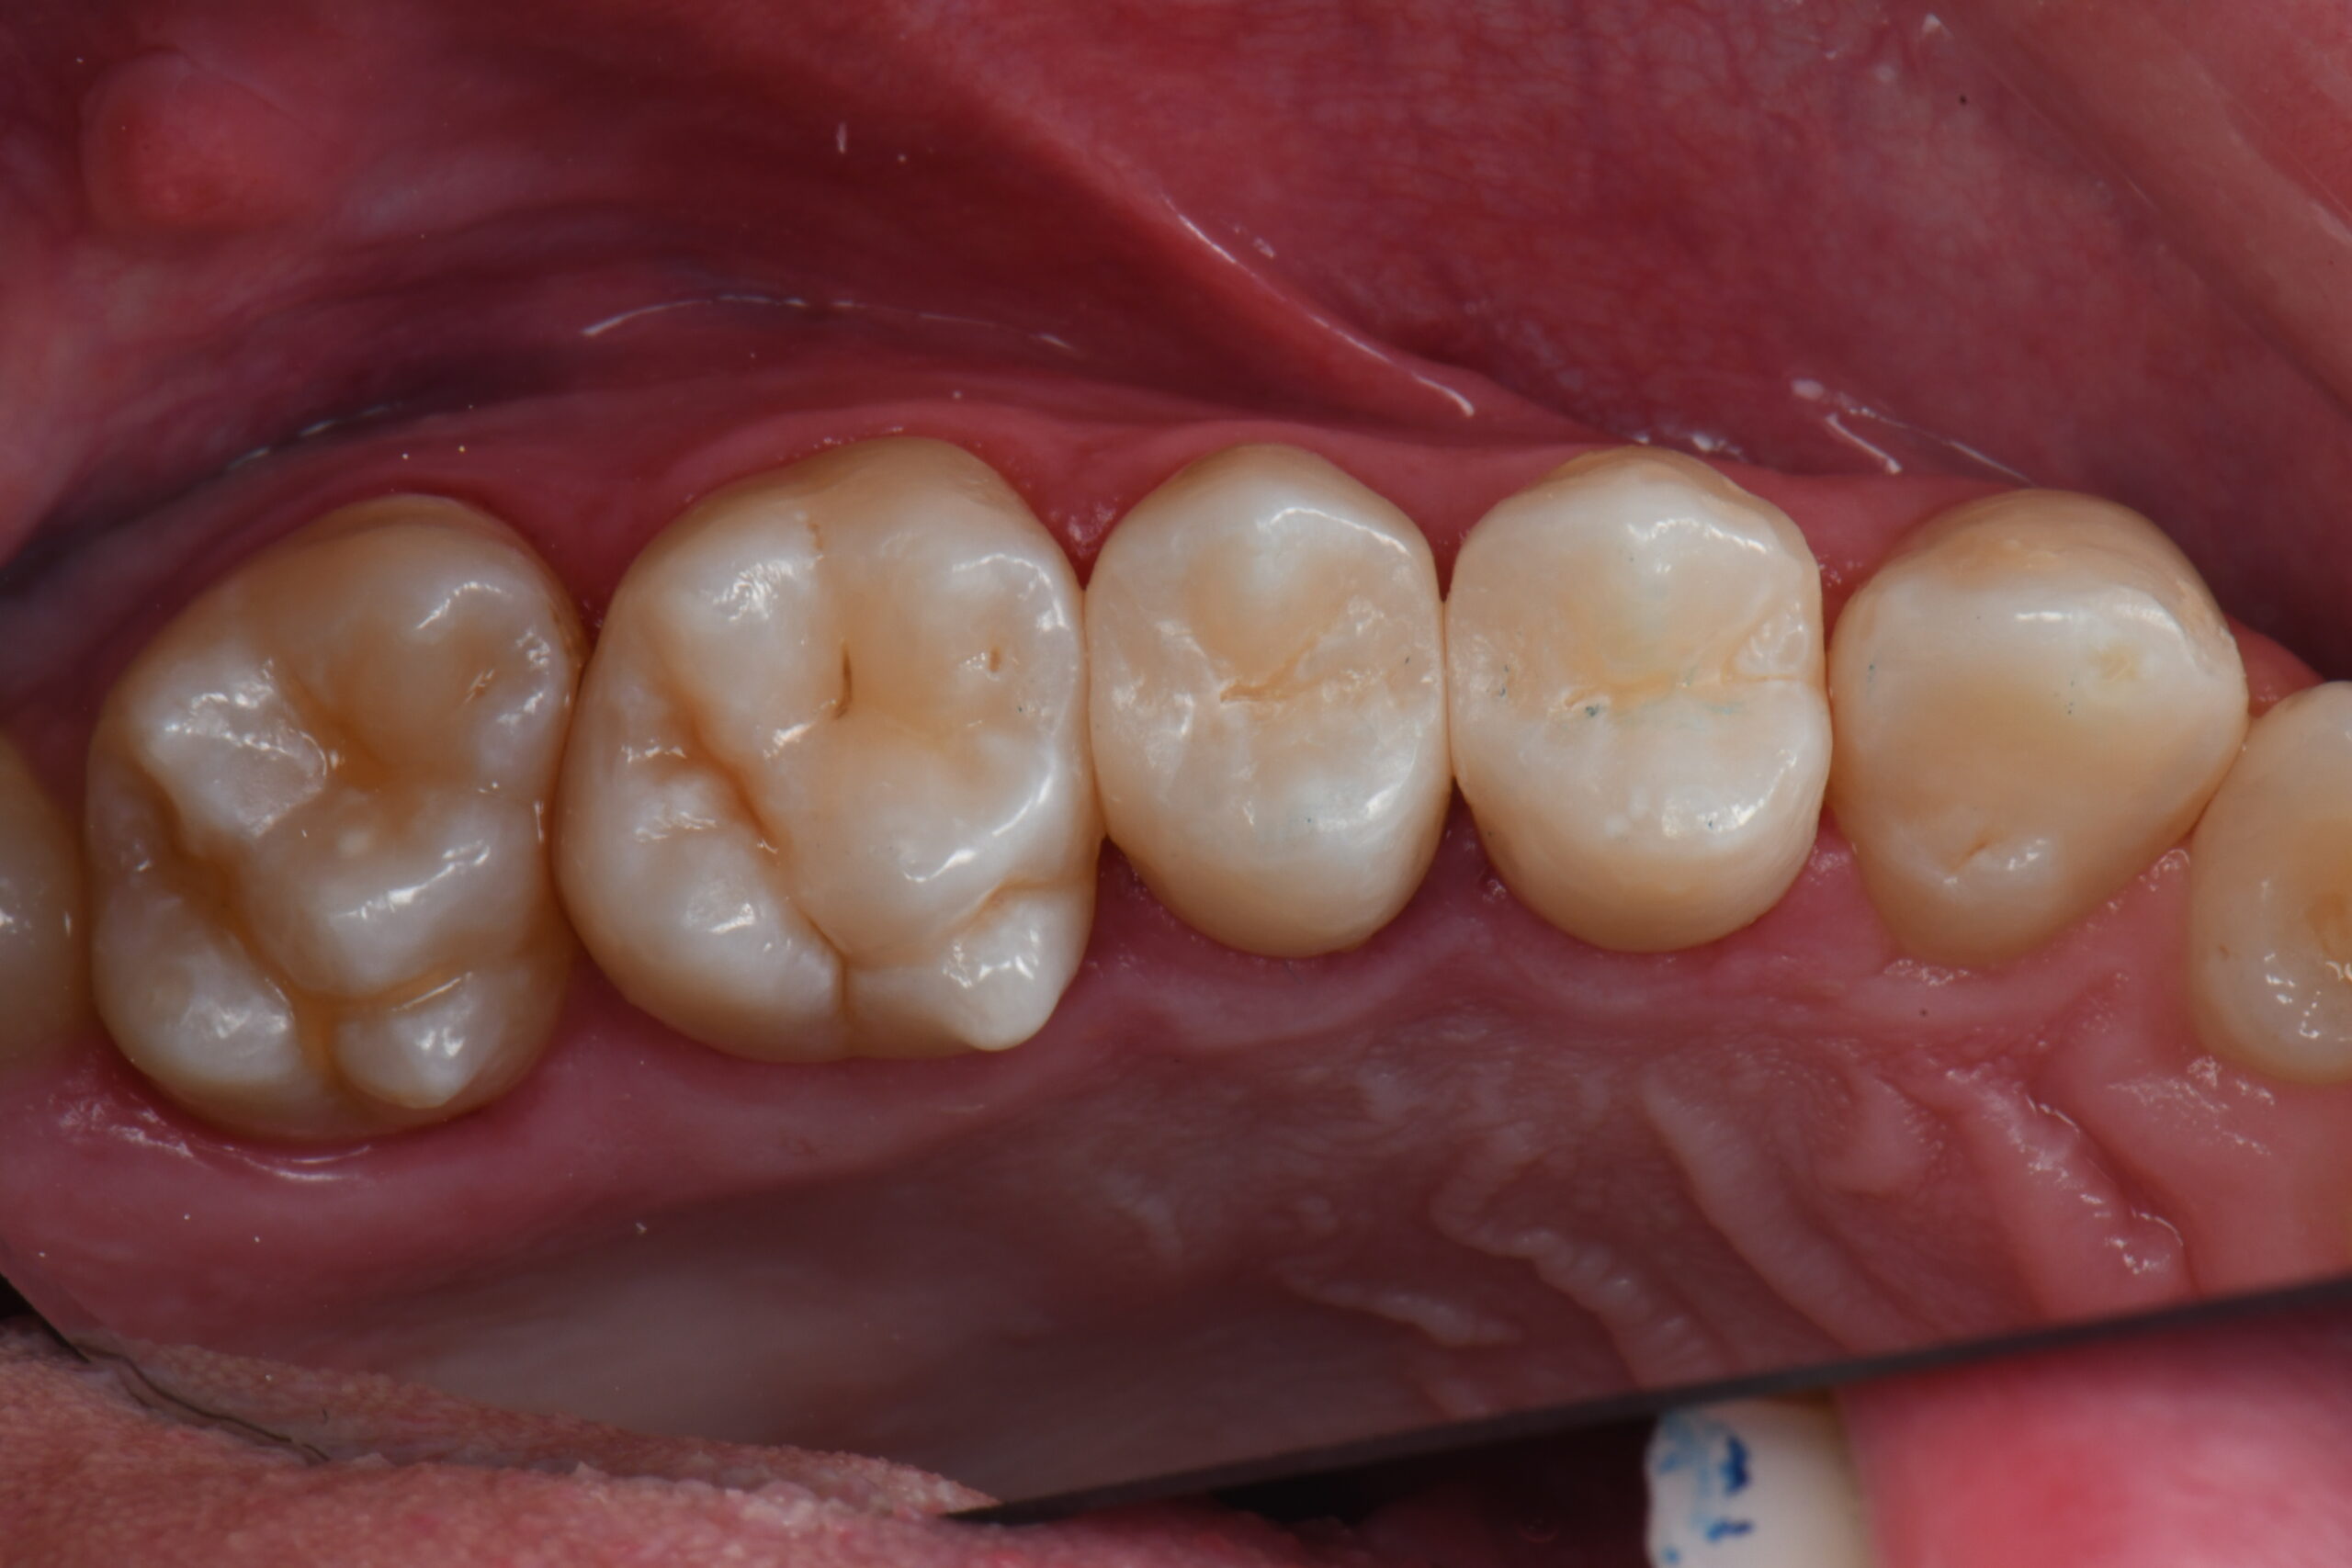

Close-up of four lower molars with visible grooves and cusps on the chewing surfaces

Post-op palatal view after rubber dam removal and occlusal adjustments.

Finally, an aspect that I always appreciate, even in the posterior teeth, is that this composite matches perfectly with the surrounding tissues also in case of a single mass technique.